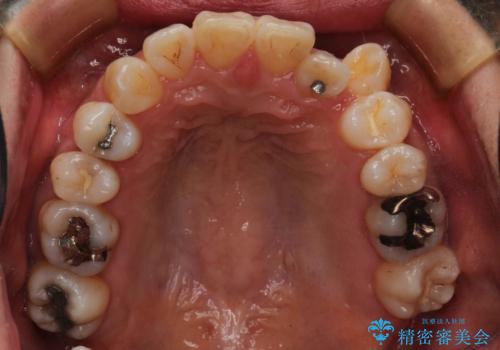

ハーフリンガル抜歯矯正 八重歯を改善する

- 小臼歯4本抜歯によるハーフリンガル・ワイヤー矯正を計画した。

シビアな八重歯がきれいに歯列にはいることにより、笑った時の印象などもかなり大きく変わります。